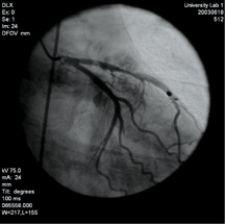

3-D volume rendering showing mid left anterior descending artery (LAD) stenosis, created using TeraRecon software.

In the past, cardiac imaging necessitated specialized equipment such as electron-beam CT. Advances in multidetector CT [MDCT] have now allowed for acquisition of motion-free sub-millimeter resolution images of the heart with ECG gating in one breath-hold. ECG gating also allows for cine imaging, assessing ventricular contractile function by reconstruction of images at different cardiac phases. The isotropic voxel nature of MDCT allows for ease of 3-D multiplanar reconstructions (MPR) and volume rendering techniques (VRT), increasing the diagnostic confidence. Due to high resolution and short acquisition time, ECG-gated MDCT holds a distinct advantage over cardiac MRI in morphological coronary imaging.

MDCT has several limitations in evaluating CAD. The dose for 64-slice cardiac CT is unfortunately [high], even with pulse modulation. The presence of arrhythmia also will markedly decrease the quality of ECG gating and the corresponding quality of images. A high heart rate above 70 will also decrease the diagnostic quality of the study. Other limitations include contrast adverse reactions and exacerbation of renal insufficiency. Extensive coronary calcification can also cause blooming artifacts, preventing adequate evaluation for significant stenosis. The moderate positive predictive value — 75 percent — limits utility of MDCT for assessing significant obstruction of native coronary arteries in high-risk patients.